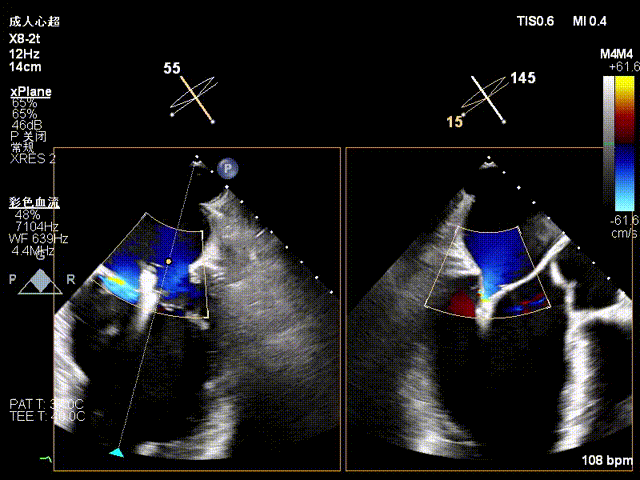

术前X-plane上彩

1、1区到3区多中央反流束组成的宽度超过25mm的巨大反流束,需要评估多夹治疗可能;